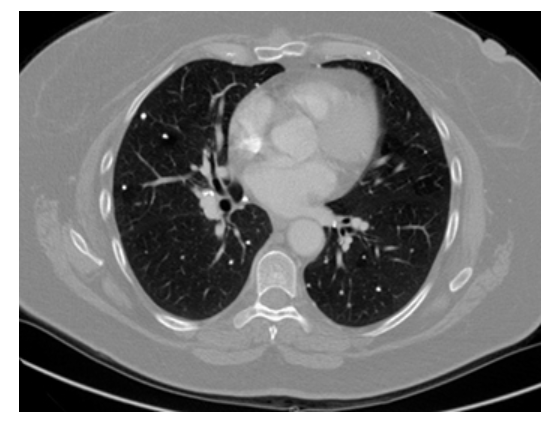

CECT shows extensive ground glass opacification of the lungs, with intense parenchymal opacification and air bronchograms. A left pleural effusion is also present.